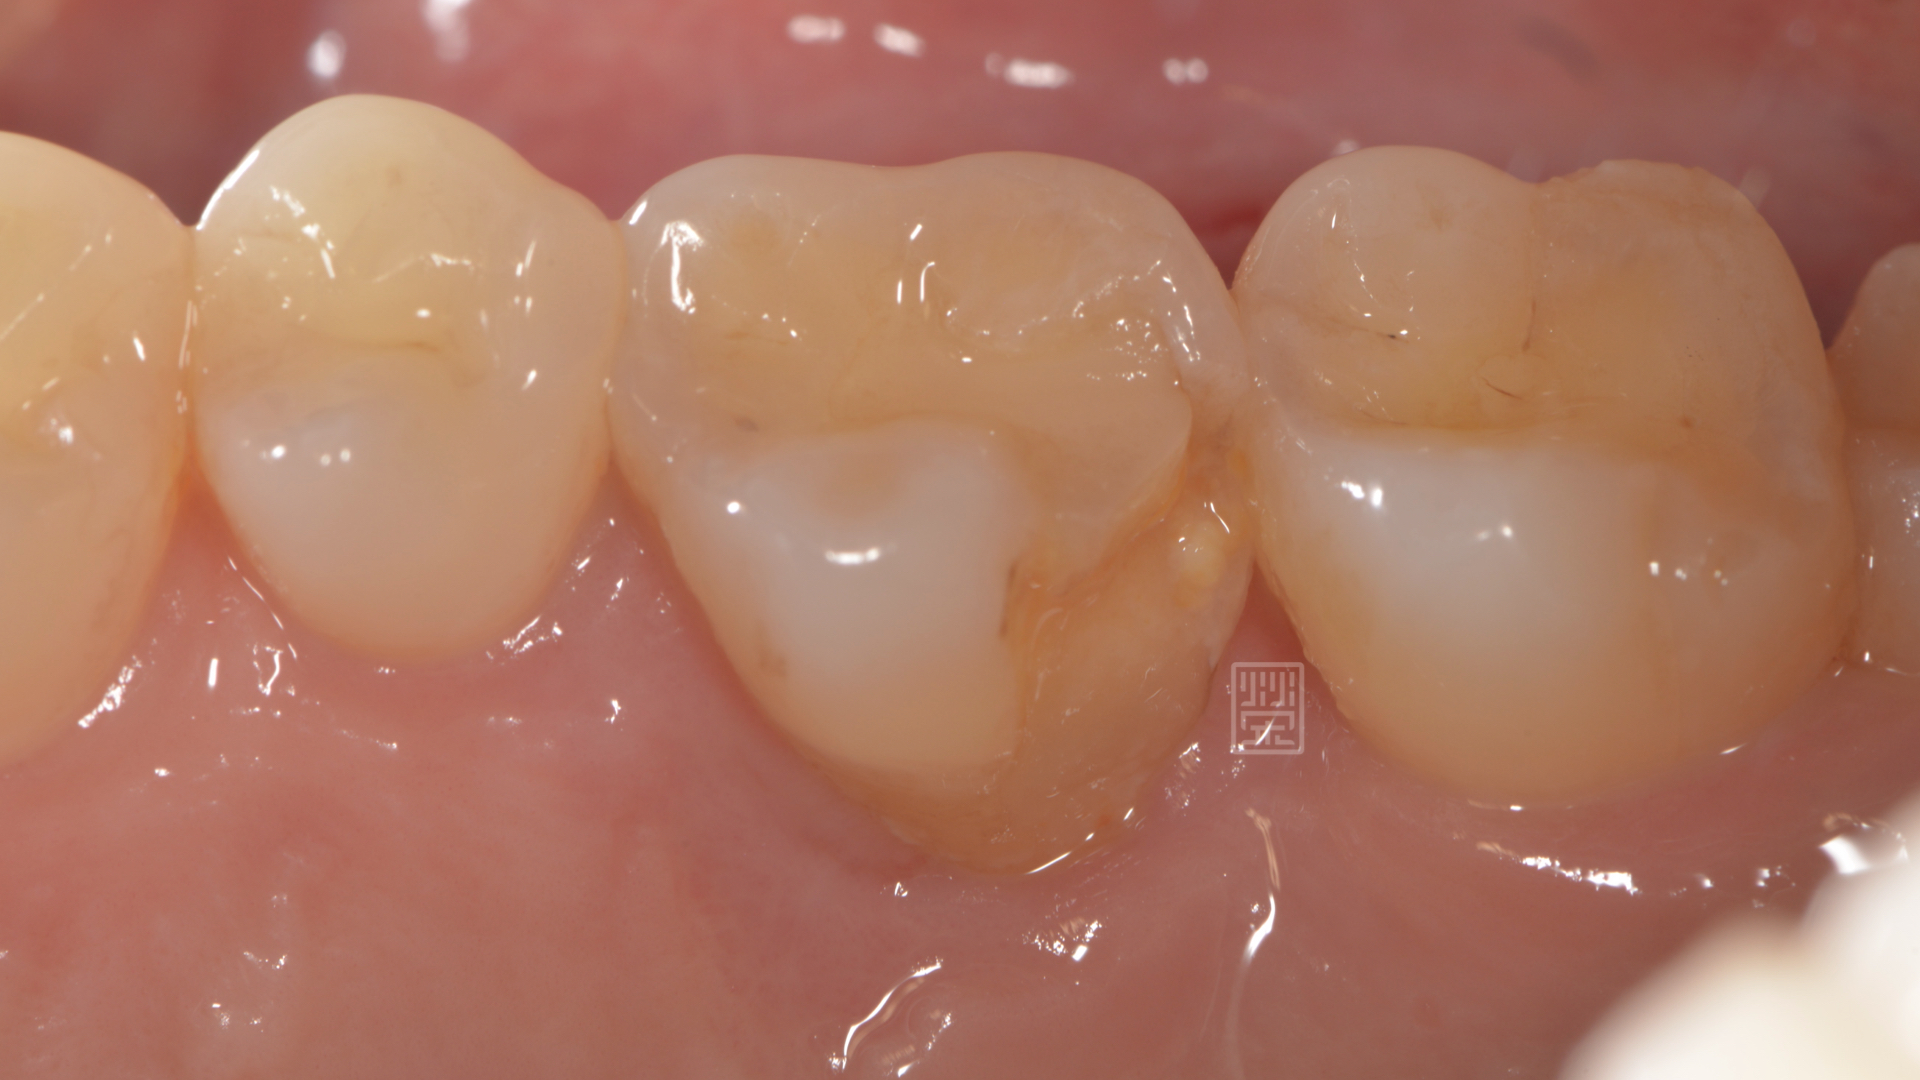

牙冠增長術後將牙齒邊緣獨立出來

牙齒邊緣修行,給全瓷嵌體足夠空間